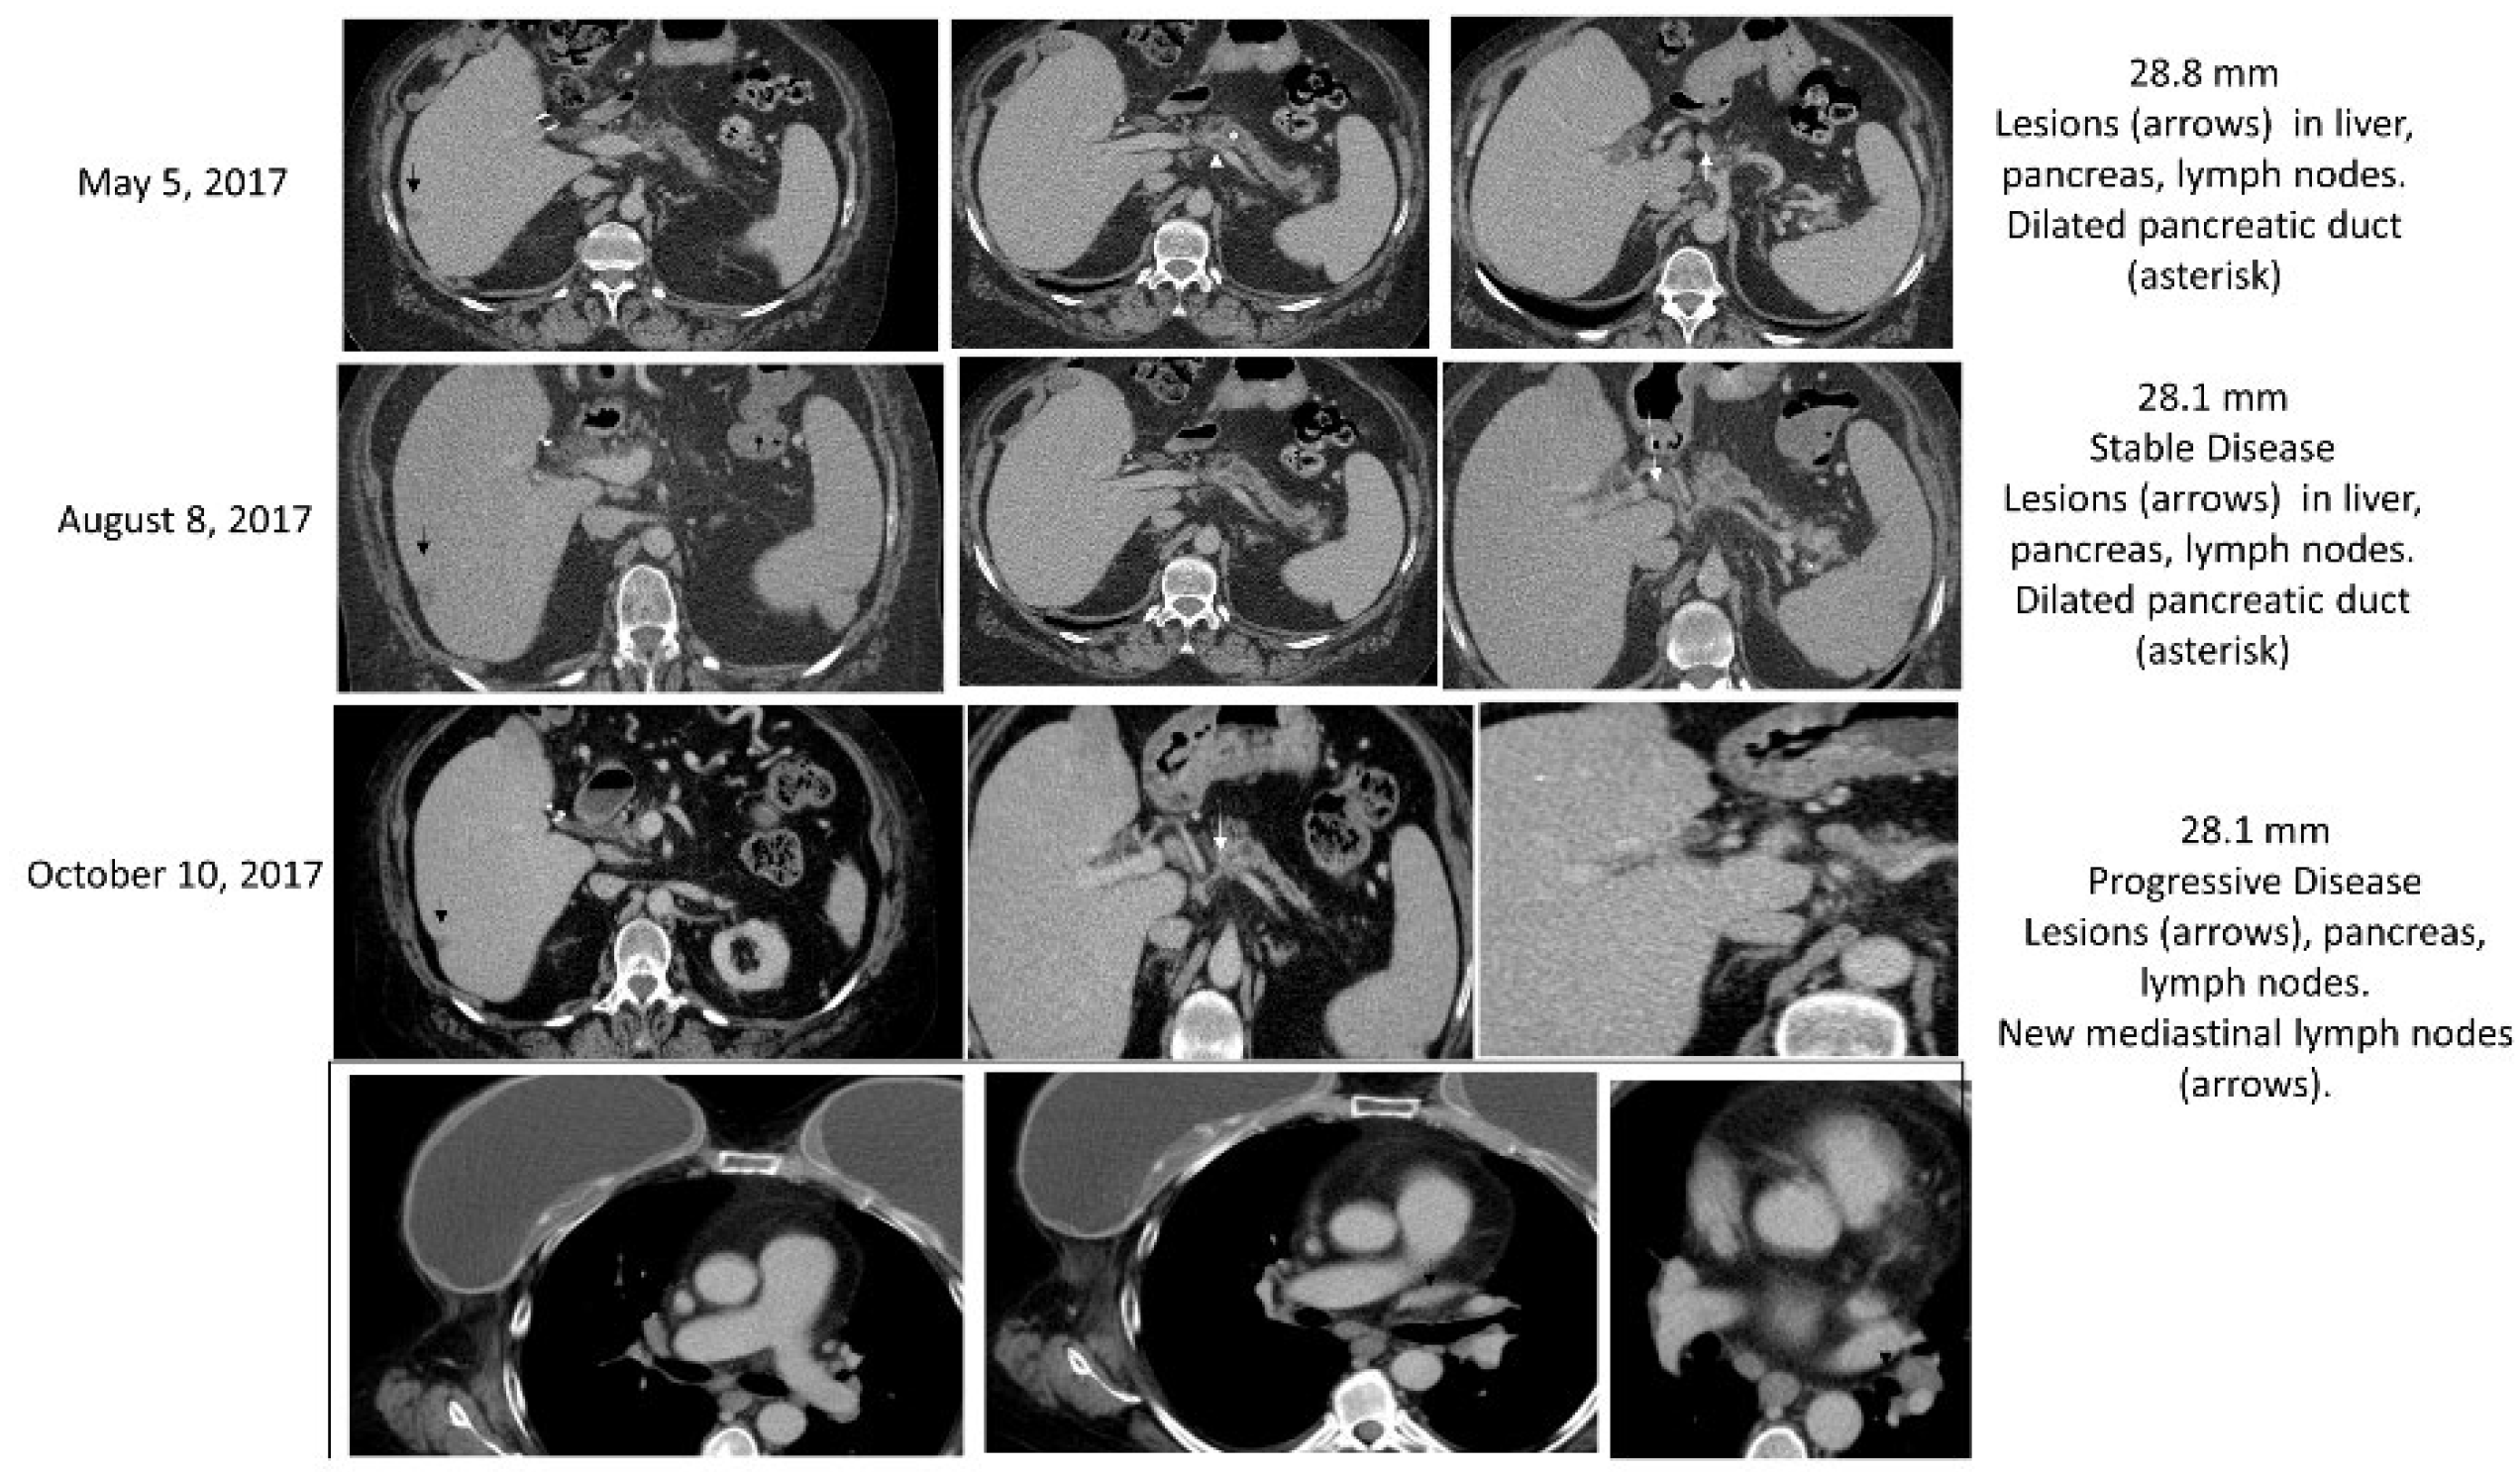

3.2.3. Case (3)